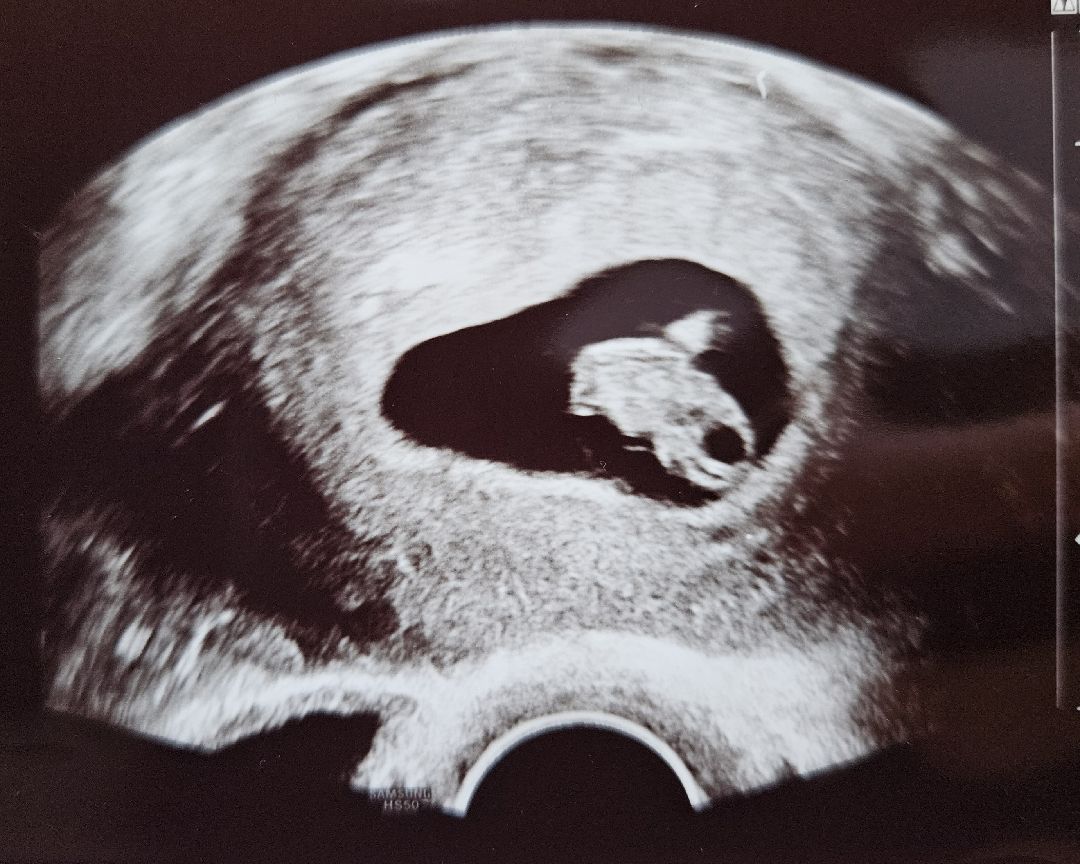

8주 0일 첫 초음파 보고 왔어요 :-)

안녕하세요 지난주 화요일 임테기로 임신 확인했는데 오늘에야 드디어 산부인과에 다녀온 독일에 사는 예비맘이에요 오늘 임신 사실도 제대로 확인하고 초음파도 처음 보고 왔어요 >_< 제 뱃속에 1.7센치 이런 꼬물이가 살고 있었다니 너무 신기하더라구요!! 예정일은 9월 11일 +/- 10일 이래요 :-) 이제 임신 제대로 확인하니 마음이 놓여요 주말엔 부모님께도 임밍아웃해야겠어요~! 모두 좋은 하루 보내시구 앞으로 자주 봬요 ^^